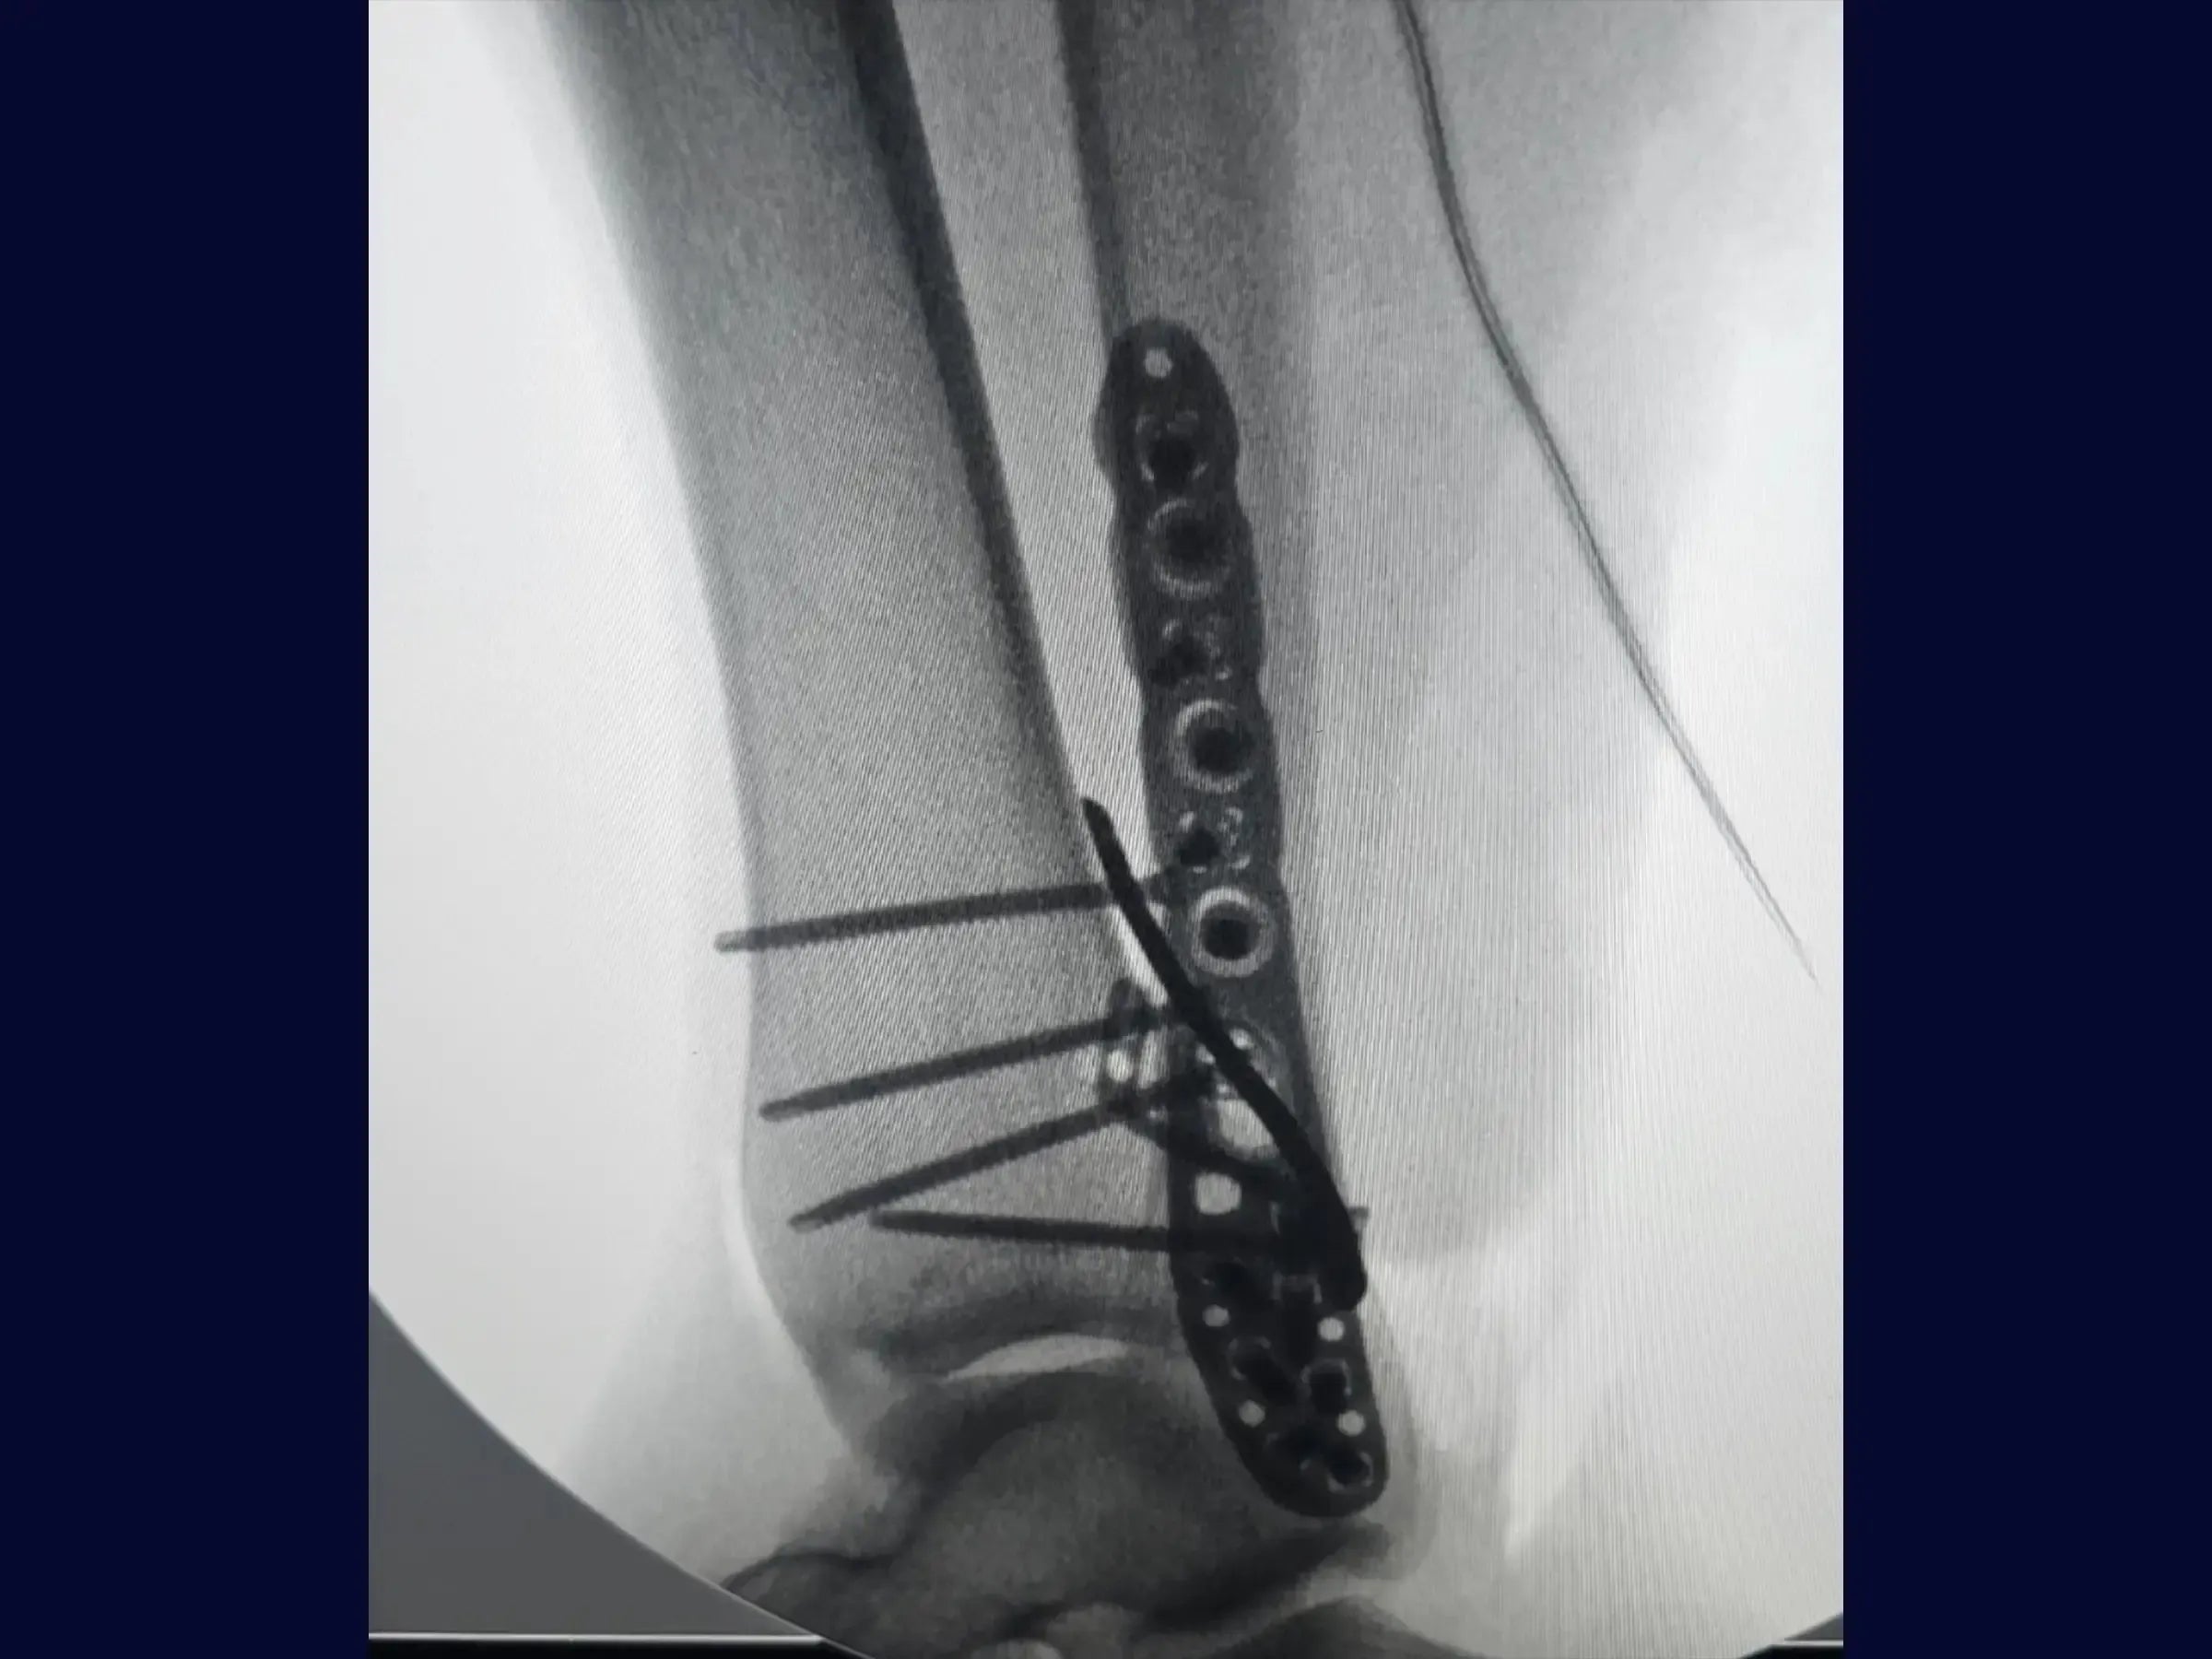

Fractura del maléolo posterior y del maléolo lateral (abordaje posterolateral único)

Dominar el abordaje de fracturas complejas de tobillo supone un reto técnico para los cirujanos ortopédicos. Esta formación proporciona una inmersión técnica en el tratamiento de fracturas de maléolo posterior asociadas con fracturas de maléolo lateral alto, mediante un abordaje posterolateral curvo único y técnicas de reducción indirecta.

- Utilización de abordaje posterolateral de curva única.

- Abordaje Peroneo Optimizado: Técnica para separar los tendones peroneos para acceder a la fractura del maléolo lateral, manteniendo la integridad muscular.

- Reducción Anatómica Precisa: Uso de fórceps para obtener la reducción anatómica de las fracturas del maléolo lateral, con identificación de los vértices.

- Fijación Estable del Maléolo Lateral: Secuencia para fijación provisional y definitiva con tornillos interfragmentarios y placa bloqueada, evitando tornillos articulares.

- Acceso Directo al Maléolo Posterior: Método para abordar el maléolo posterior a través del mismo acceso, rompiendo la fascia y reflejando los tendones para su visualización.

- Reducción indirecta efectiva del maléolo posterior: demostración de la técnica de reducción indirecta del maléolo posterior mediante la acomodación de la placa y la introducción de tornillos, minimizando la exploración.